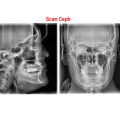

[PANO / CEPH / CBCT / MODEL SCAN]

Green X is an advanced 4-in-1 digital x-ray imaging system that incorporates Pano, Ceph (optional), CBCT, and Model Scan. With Vatech’s extensive experience in the dental imaging field, the Green X provides high-quality images with lower radiation by combining image processing. This will improve your diagnostic accuracy and lead to increased treatment planning and patient satisfaction.

Function: CT + PANO + CEPH + Model Scan

Scan Time: PANO = 4.0 sec/ 14.1 sec, CEPH = 1.9 sec/ 4.9 sec, CBCT = 2.9 sec/ 9.0 sec